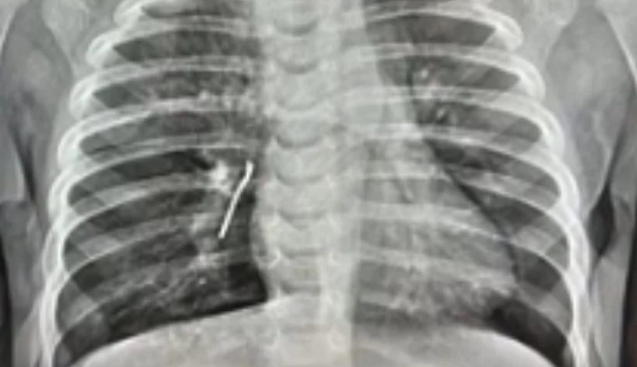

Алайда баланың жағдайы күрт нашарлап, қатты ентігу пайда болған. Ол шұғыл түрде ауруханаға жатқызылып, қабылдау бөлімінде рентген жасалды. Түсірілім өкпеде бөгде зат бар екенін көрсетті.

Бронхоскопия барысында дәрігерлер тағы бір бөгде затты – күнбағыс дәнінің қабығын анықтады. Дәрігердің айтуынша, металл зат ұзақ уақыт бойы астма белгілерін "жасырған", соның салдарынан бала басқа аурудан емделген.